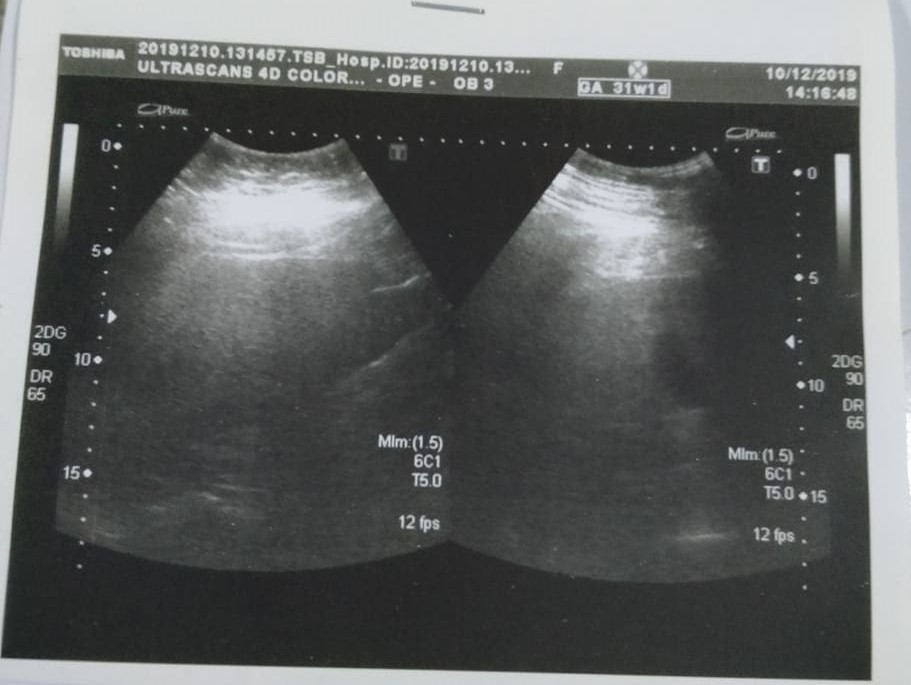

Asking for Other, Female, 85 years old, pakistan

swelling on arms ,feet and pain in kidney region as well as quite blood has gotten quite thick please see reports attached below and guide thanks